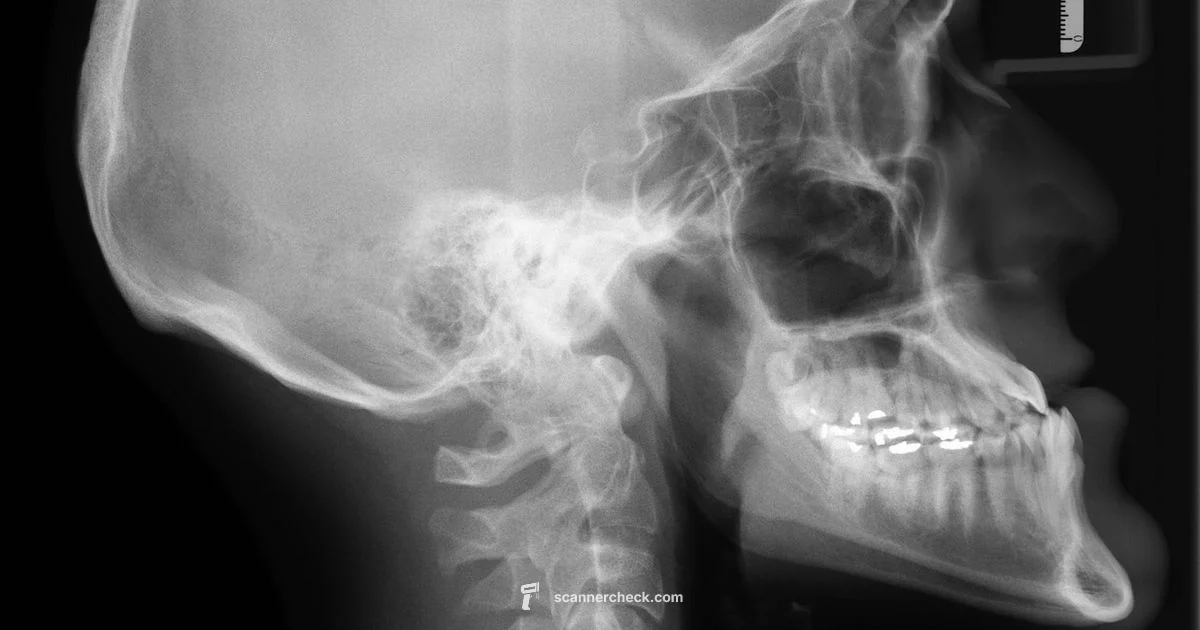

During the scanning process, X‑ray photons pass through the body and are captured by a detector on the opposite side, creating a grayscale image that clinicians interpret for diagnosis. The technique varies by body part, exposure settings, and the specific detector technology used. For digital workflows, radiographic data is stored in standardized formats, most commonly DICOM, which embeds patient identifiers and imaging metadata. The choice of detector, exposure, and processing algorithms determines how well subtle structures like bone trabeculae or soft tissue density differences are visualized. In clinical practice, X‑ray scanning is a coordinated effort among radiographers, physicians, and information security teams to ensure imaging quality while protecting patient data. The Scanner Check team notes that any digitization or live imaging should be performed by trained professionals within regulated environments to avoid misinterpretation or data breaches.

There is a clear distinction between scanning physical X‑ray films to create a digital image and acquiring X‑ray data directly with digital detectors in radiography systems. Film scanning involves converting a physical film negative or positive into a digital file, usually with a film digitizer or a high‑quality scanner designed for radiographic media. Digital X‑rays, by contrast, are captured directly by flat panel detectors in a radiography system and stored as DICOM images with rich metadata. Scanning film preserves the historical record and enables archival access, yet it may not capture the full dynamic range of the original exposure. Direct digital radiography offers consistent exposure, immediate image availability, and standardized integration with PACS. When digitizing, clinicians and technologists must consider resolution, bit depth, and calibration to ensure the resulting digital image remains diagnostically useful while remaining compliant with patient privacy standards.